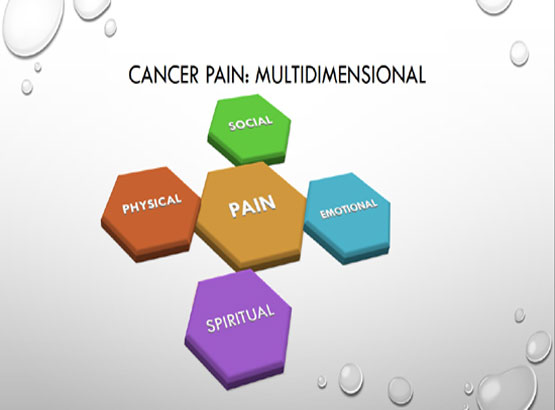

Fields of expertise: Dr Arghya Mukherjee has special interest in Ultrasound guided acute and chronic interventional pain management procedures. He performs Fluoroscopy guided interventional pain management procedures for chronic and cancer pain as well with expertise.

Pain management awareness: Dr Arghya regularly participates and organises awareness programs. He has been the organising secretary for CME on Cancer Pain 2017, 2018 and 2019 and WBSSPCON 2018.